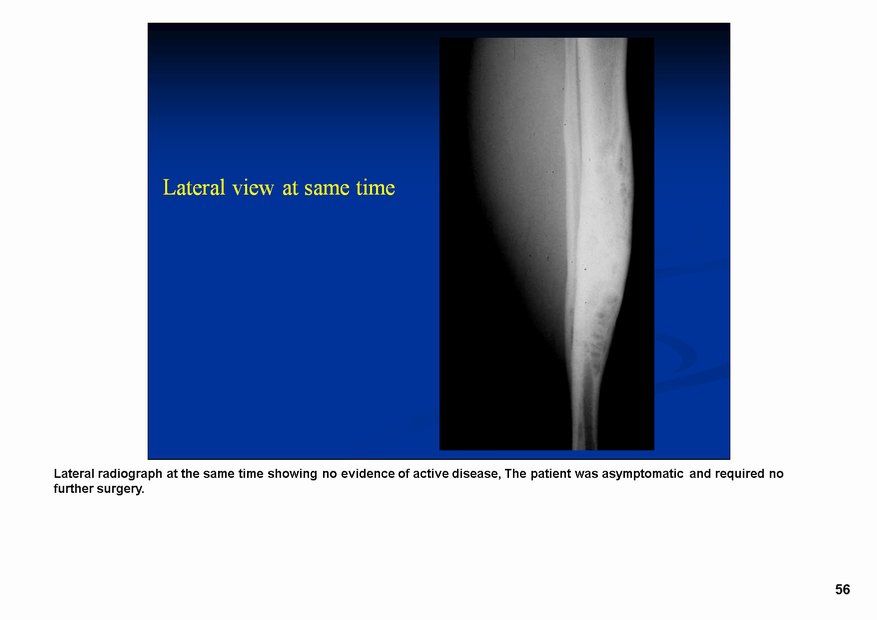

Классический радиологический облик